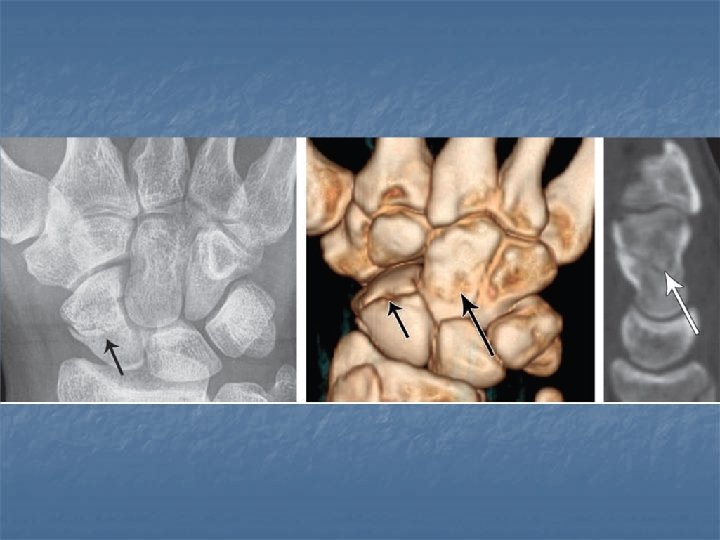

Scapholunate dissociation n n Results from injury of the scapholunate ligament Radiographicaly diagnosed by Terry Thomas sign due to widening of the space between the scaphoid and lunate more than 2 mm

Terry Thomas sign

Rotatory subluxation of scaphoid n n n Related condition to scapholunate dissocaition where there is in addition rotation of the scaphoid along its long axis Radiographically diagnosed by signet ring sign: volar tilt of the scaphoid makes it appear foreshortened with its tuberosity seen end on giving a cortical ring. Radiographs in dorsovolar view should be in the neutral position or with ulnar tilt for this sign to be reliable one

Neutral position signet ring sign Radial tilt Normal scaphoid